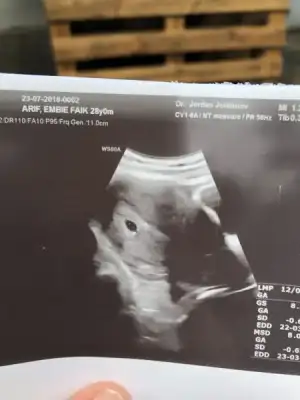

Cuma günü gittiğimde benimde boyledi bir daha ne zaman gideceksiniz kalp atışı içinGeldim kızlar

Çok şükür gördük keseyi

1 hafta geriden gidiyor, ama olsun

Darısı kalp atışına inşallah canım kaçıncı haftada gördün keseyiGeldim kızlar

Çok şükür gördük keseyi

1 hafta geriden gidiyor, ama olsun

Gozun aydin canim simdi geri olur iki gun sonra ileri olur daha cok degisir o durum hic kafani takmaGeldim kızlar

Çok şükür gördük keseyi

1 hafta geriden gidiyor, ama olsun

Takvime göre 5+6 olmam lazımDarısı kalp atışına inşallah canım kaçıncı haftada gördün keseyi

Ama ölçümde 5+2 çıktı cnm

Oyy Allah yardımcın olsun canım rabbım bu bebışı verdyse bırbıldgı vardr sanada guvendgı için üstesınden kalkabılecegın için vermstr sakın sıkma canını en dogru kararı vermıssın kesnlıkle aldrma Rabbım her ıkısnede saglık versınSelam arkadaşlar bende ikinci kez Mart annesi olucam. Herkese sağlıklı ve vakitli Doğumlar diliyorum. 4 aylık prematüre bebeğim var Mayıs’ta doğması gerekirken martta doğdu. Korunurken hamile kaldığımı öğrendim herşeyin hayırlısı diyorum. Dün bebeğimin kesesini gördü. 8 mm kalp atışı için haftaya gideceğim. Sezeryan yaram henüz iyileşmedi normalde riskli gebeyim sezeryandan dolayı riskim iki kat arttı Allah’a teslimim bebeğimde bir sorun olmadığı sürece asla aldırmayı düşünmüyorum. Herkese selamlar